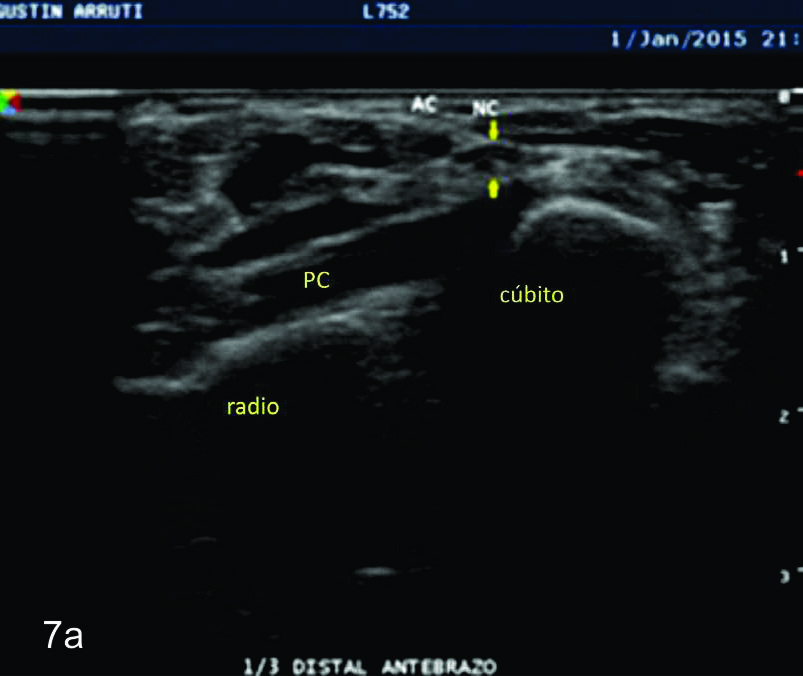

Figura 7

Nervio cubital

Serie de cortes axiales del nervio cubital desde su origen a nivel del hueco axilar hasta su terminación a nivel del canal de Guyon. Se identifica el mismo señalado por flechas amarillas y con las letras NC. AH-arteria humeral, PC- músculo prondador cuadrado, P- hueso pisciforme, Línea roja- ligamento anular del carpo, Línea amarilla- túnel de Guyon, Flecha azul- Arteria cubital-. A-tercio distal antebrazo, B- canal de Guyon.